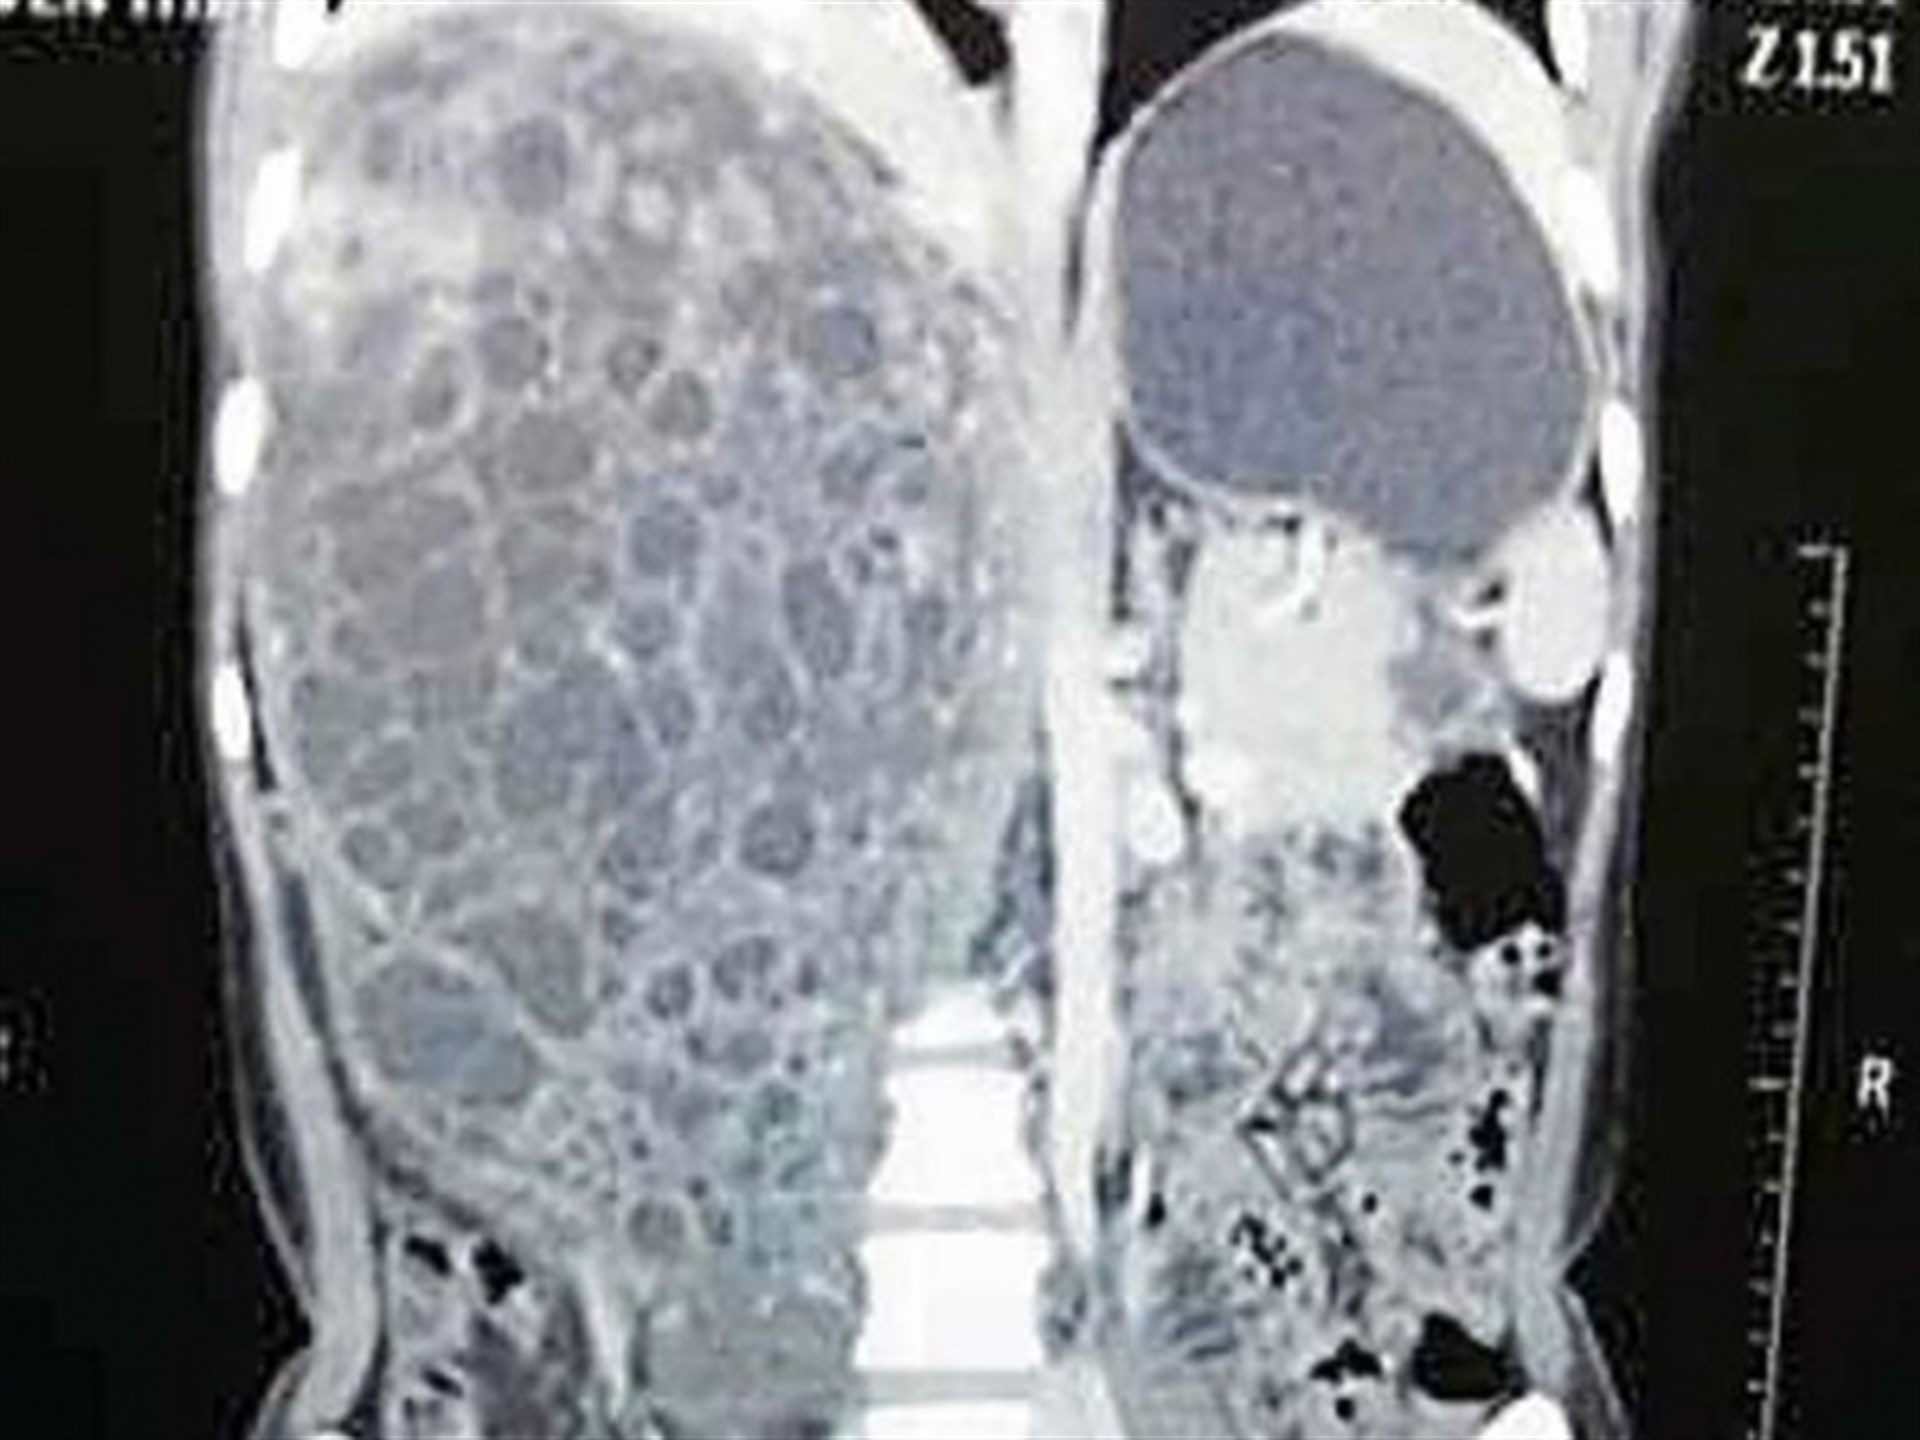

Una tomografía computarizada reveló que el tumor había cubierto casi por completo al riñón derecho, comprometiendo la vida de la paciente.

Entre otros síntomas la mujer mostraba dolor persistente en el lado derecho de su cuerpo, además de que estaba llegando orina a su sangre debido a la masa de 31 por 19 centímetros, publico The Times of India.

Los médicos destacaron que la complejidad del problema y de la intervención puede apreciarse si se comparan los 110 a 140 gramos de peso promedio de un riñón normal, con los cinco y medio kilogramos del tumor.